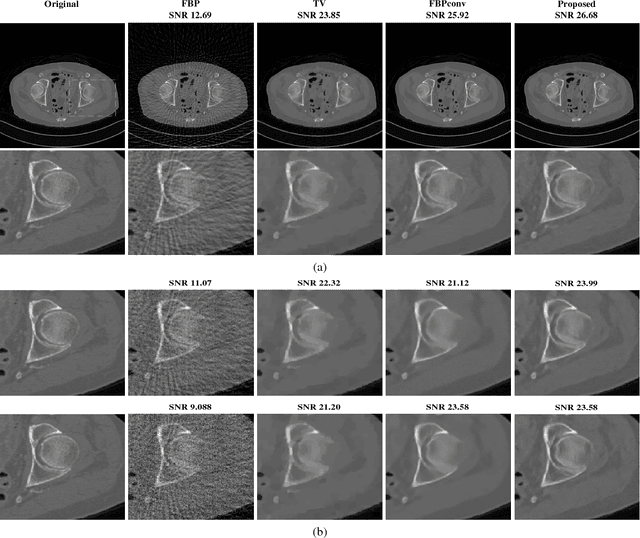

We present a new method for image reconstruction which replaces the projector in a projected gradient descent (PGD) with a convolutional neural network (CNN). CNNs trained as high-dimensional (image-to-image) regressors have recently been used to efficiently solve inverse problems in imaging. However, these approaches lack a feedback mechanism to enforce that the reconstructed image is consistent with the measurements. This is crucial for inverse problems, and more so in biomedical imaging, where the reconstructions are used for diagnosis. In our scheme, the gradient descent enforces measurement consistency, while the CNN recursively projects the solution closer to the space of desired reconstruction images. We provide a formal framework to ensure that the classical PGD converges to a local minimizer of a non-convex constrained least-squares problem. When the projector is replaced with a CNN, we propose a relaxed PGD, which always converges. Finally, we propose a simple scheme to train a CNN to act like a projector. Our experiments on sparse view Computed Tomography (CT) reconstruction for both noiseless and noisy measurements show an improvement over the total-variation (TV) method and a recent CNN-based technique.